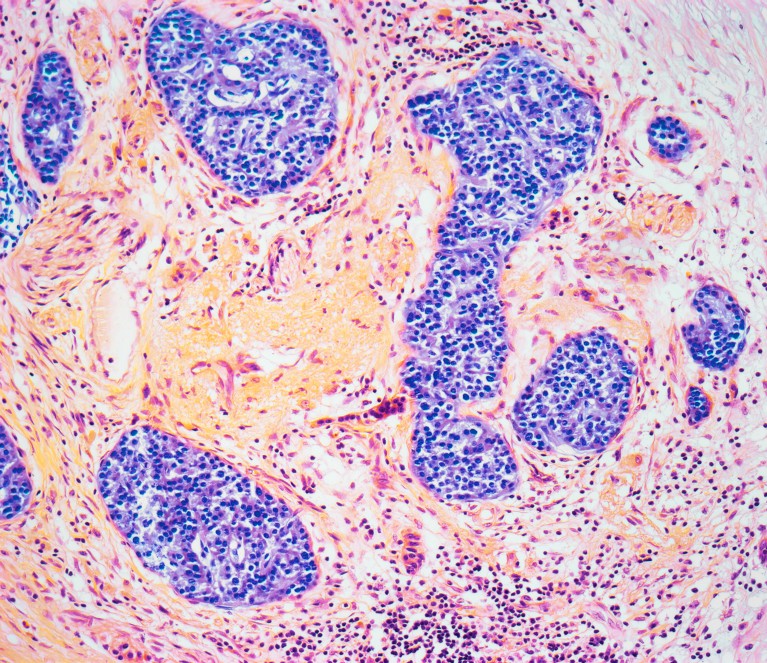

The condition called pancreatitis causes inflammation of the pancreatic tissue (pictured). Credit: Steve Gschmeissner/Science Photo Library